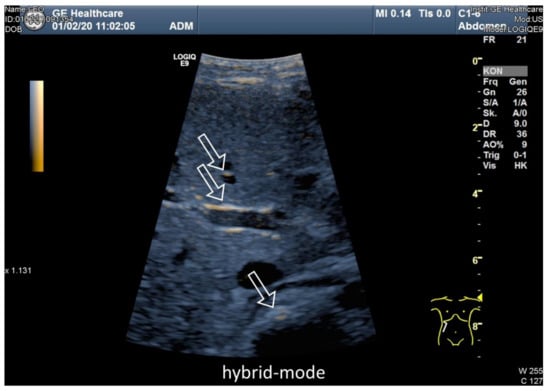

3.3. Ultrasound Examination of Intestinal Absorption